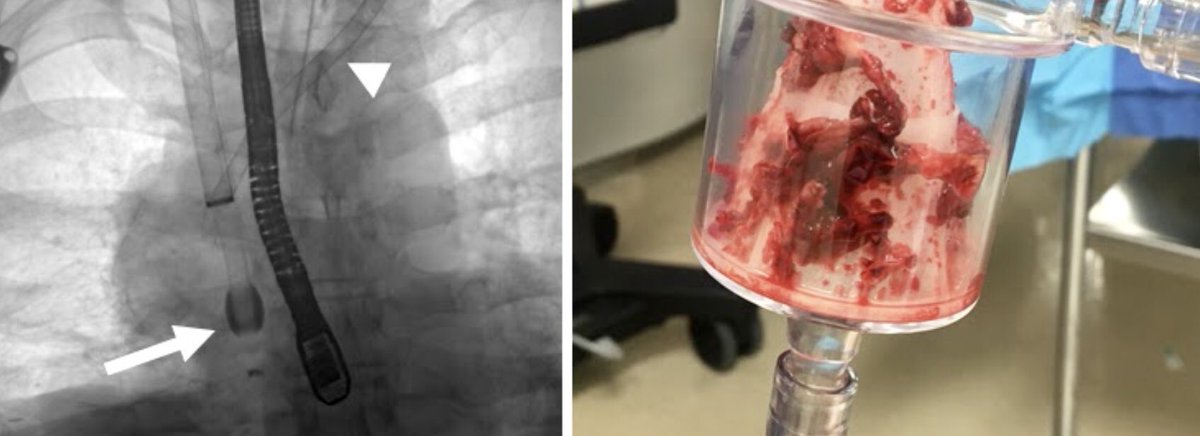

Right Atrial Thrombus??

Have no fear AngioVac is here! #IRAD#SingleSessionSuction#AngioVac#Venous Disease#WeAreIR@JonnyMoriarty@medravi@jhussainMD@EJJohnsonMD@iRadRaj@IRadNAP@KyleCooperMD@AlexCVIR@mmkhayatmd@JBundyRad@svmehtamd@JVIRmedia@_backtablepic.twitter.com/B7uNUrG8Vn